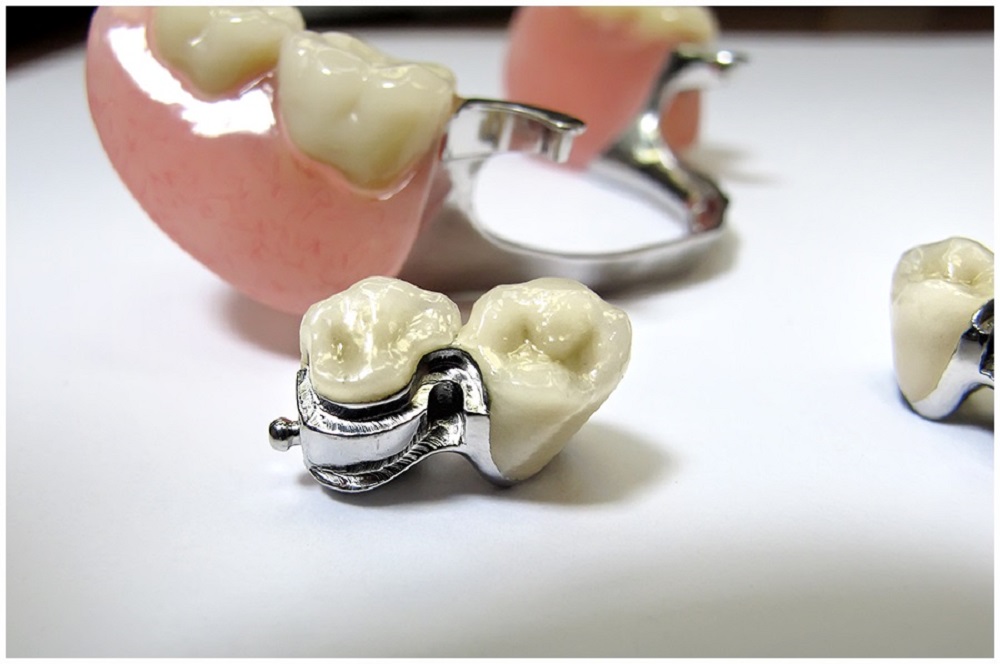

Восстановление физиологичной жевательной поверхности — т. е. пломба должна повторить природный рельеф зуба, а, возможно, в некоторых случаях даже его улучшить.

Зубы — наши природные жернова! Они тоже имеют «зубцы» — жевательные бугры, которые должны точно входить в выемки жевательной поверхности — - «фиссуры» — зубов на другой челюсти. Только так мы можем качественно жевать. Если наши зубы будут гладкими, как каток, мы ничего не прожуем, эффективность зубов потеряется!

Поэтому хороший врач во время лечения все время просит пациента прикусить «копирку» и тщательно восстанавливает все детали «зубного рельефа».